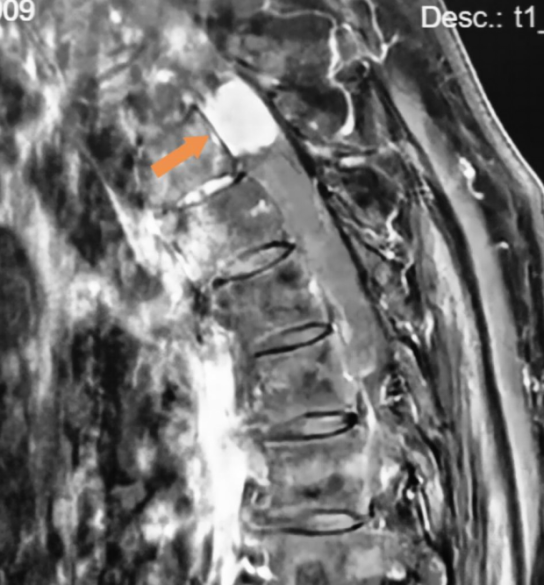

术前胸椎MRI增强检查

MRI平扫和增强是脊膜瘤的首选诊断方法,可以帮助我们确定肿瘤的边界及其与周围脊髓等神经结构的关系,是术前评估,术后确认是否充分切除以及肿瘤是否复发的可靠手段。脊膜瘤在MRI上特征性的图像为在增强MRI上出现的“硬膜尾征”,肿瘤局部的硬脊膜增厚,呈现线样强化并与肿瘤紧密相连。(图中黄色箭头像尾巴一样的亮线条就是“硬膜尾征”)